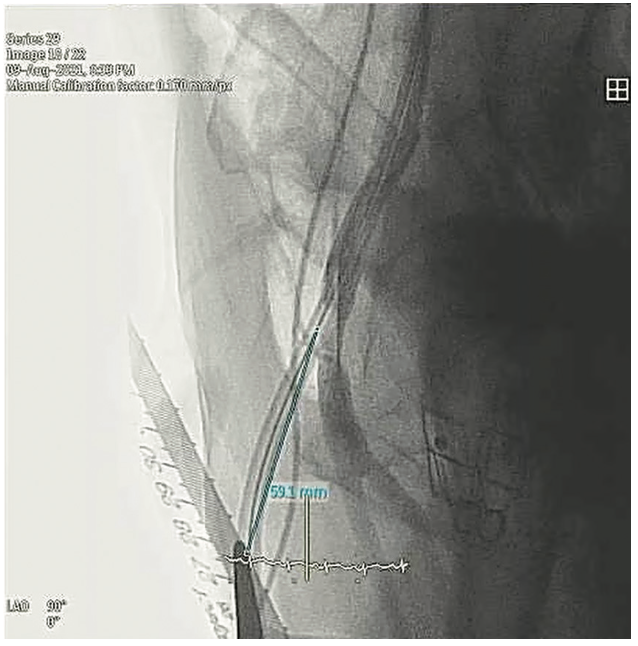

3. A ruler with a sterile cover was placed parallel to the Impella driveline in the coronal plane under fluoroscopy (Figures 1-2).

4. Without changing the alignment of the ruler, an angiogram at a left anterior oblique 90-degree (true lateral) angle was performed, with contrast injected via a cross-over internal mammary (IM) catheter. Apart from measuring the skin-arteriotomy distance, this angiogram also confirmed the position of the arteriotomy, which was well above the femoral bifurcation.

5. Calibration of the length was done, and the distance between the skin (marked with the metal pointer) to the Impella arteriotomy was measured (Figure 3).